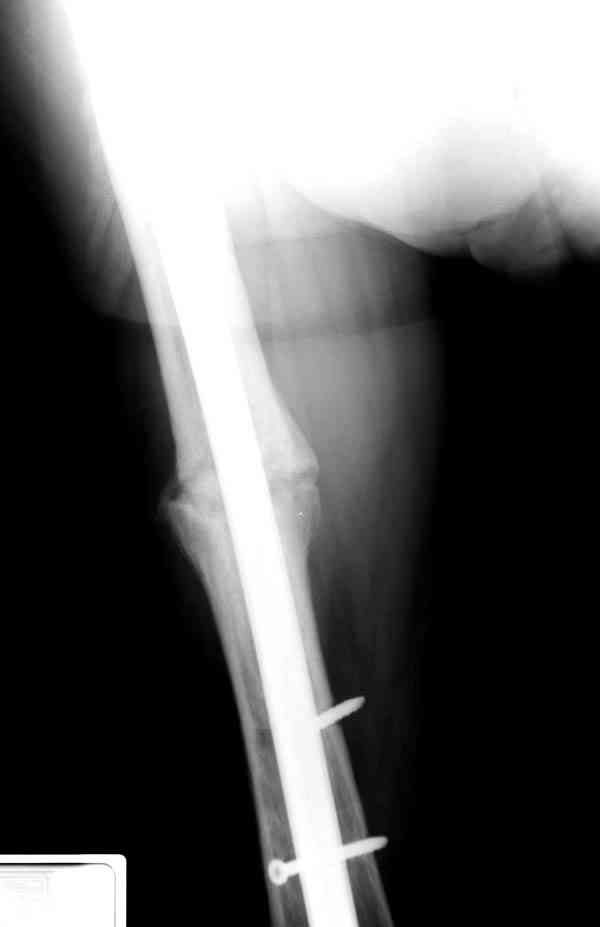

Сросшаяся малоберцовая как распорка привела к образованию ложного сустава. В таких случаях удаляем сломанный штифт и проводим стимуляцию ложного сустава рассверливанием. Рассверливание канала создает стимуляцию на месте ложного сустава, и динамический вариант блокировки штифта с большим диаметром создаст стабильность. Ранняя нагрузка после остеотомии малоберцовой приведет к сращению ложного сустава.

Приспособление для удаления сломанных штифтов и наличие ЭОП облегчит задачу. При отсутствии крючка тогда можно применить обычный длинный ball pointed guide wire от интрамедулярного набора. Проволока, пропущенная за пределы гвоздя и зажатая другая вытащат сломанный конец штифта без проблем.